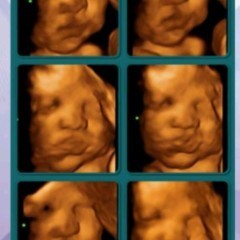

9months, baby boy

Kabuwanan ko na po, any tips po para makaraos na at hndi umabot sa due. #firstbaby #pregnancy